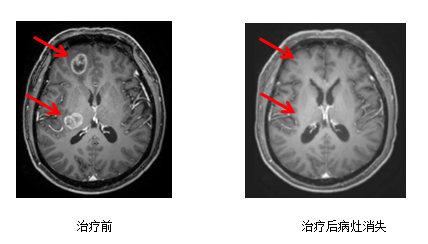

病例二:颅内多发转移瘤

治疗前治疗后病灶消失